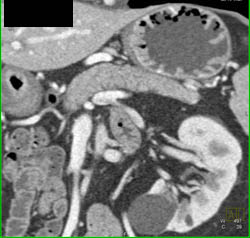

Diagnosis

Antral Carcinoma